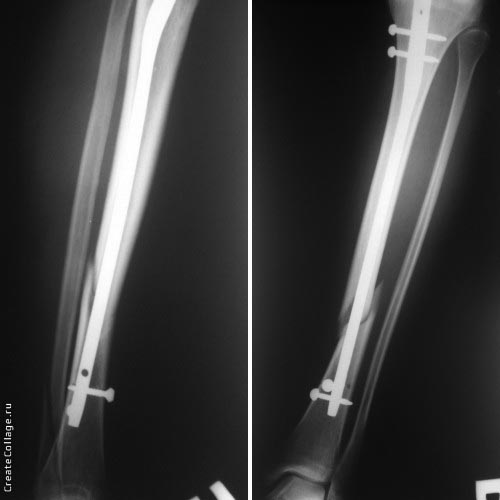

Хотя, по существу, гвоздь действительно короткий, и не смотря на это, заблокирован дистально только одним винтом - не стабильно

1. Гвоздь ОЧЕНЬ коротковат. Нет репозиции большеберецовой, гвоздь в дистальном отломке пошел по задней стенке.

Разбор любого случая кому-то поможет лучше ориентироваться в решении вопросов, потому что в нашей работе встречаются разные связанные и несвязанные с мастерством хирурга ситуации. Возможно, отсутствие полного набора гвоздей повлияло на выбор короткого имплантата, имеется угловая и ротационная деформации. Независимо от локализации, стабильность создается, когда гвоздь проксимально не глубже 1.5 см (облегчает удаление) и дистально доходит до epiphyseal scar.

Мнение о том, что гвоздь сделает репозицию не всегда соответствует истине. Снимки показывают на неудачную попытку исправить направление гвоздя с помощью “поллеров”. Прием возможен только тогда, когда проход риминга в центре канала, иначе толкать гвоздь некуда.

Здесь несколько снимков изолированного перелома большеберцовой с интактной малоберцовой. Weber clamp, блокирующие спицы и риминг в центре канала отрепонировал перелом....

В нашем распоряжении были все размеры гвоздей, но взяли этот.

Следующий размер на 15 мм больше и доходил до уровня сустава. Иногда даже самая идеальная фиксация не гарантирует сращение, надо оставить запас для динамизации. Дистально исчерпан лимит, а проксимально достаточно места...